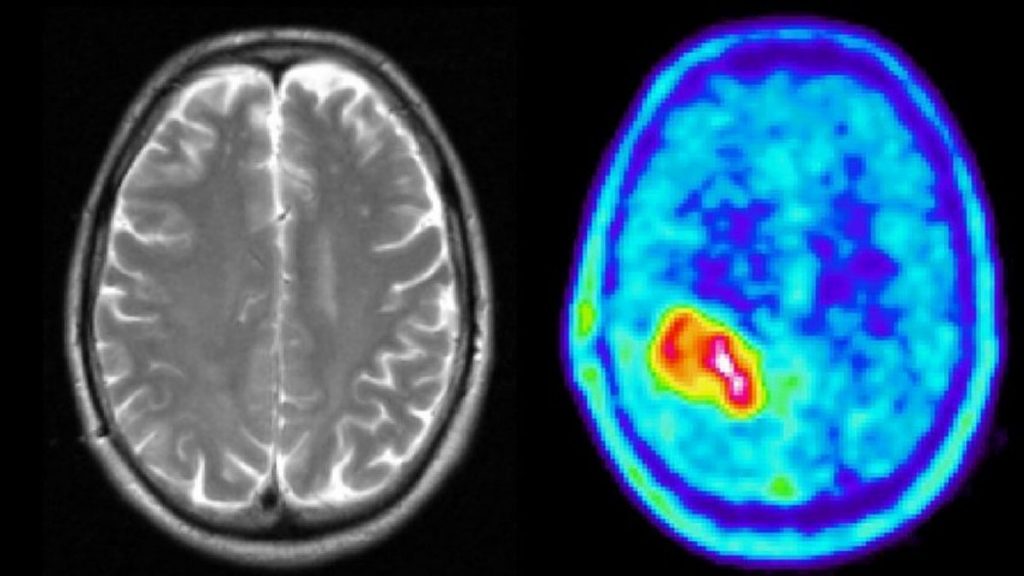

El médico debe analizar si el cáncer está propagado y el lugar donde se originó. De esta manera se establece la etapa o estadificación del cáncer y se decide el mejor tratamiento para el paciente.